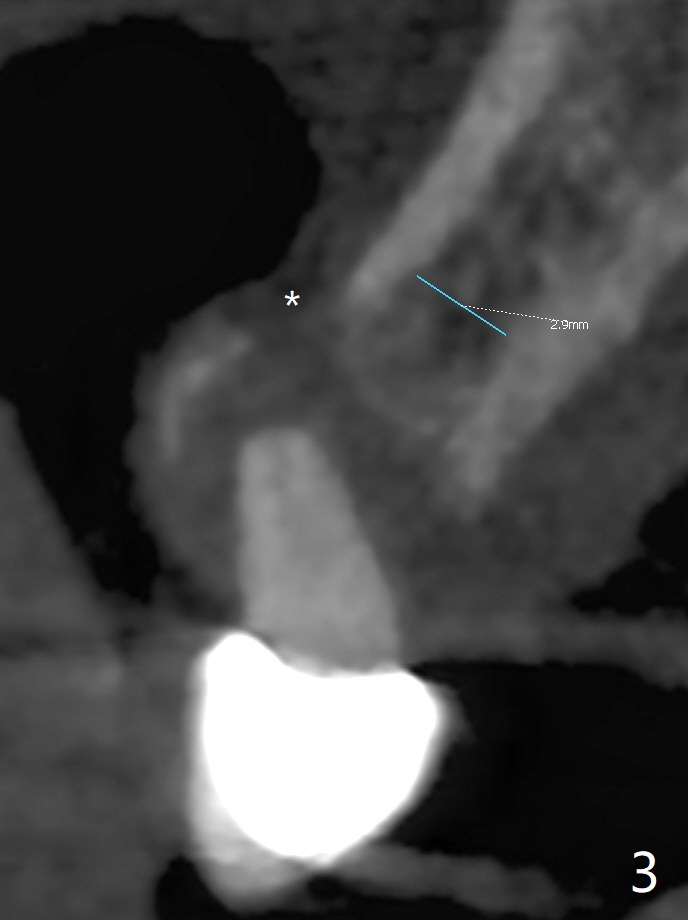

A 52-year-old man requests extraction of the mobile deciduous canine for implant (Fig.1). Use sticky bone (Fig.2 red) to maintain the canine prominence (>). In fact, there is apical perforation of the deciduous canine (Fig.3-5: *). Before bone graft, place a small piece of PRF for repair. The patient refuses to close the diastema between #8 and 9 (Fig.4 ^). Since the cancellous bone is 2.9 mm (Fig.3), it is safe to place a narrow implant (Fig.7). Return to Protect Graft Clindamycin 手术 15 Xin Wei, DDS, PhD, MS 1st edition 04/28/2021, last revision 05/27/2021